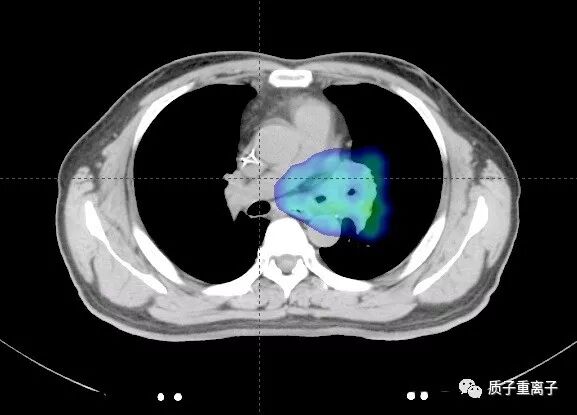

质子治疗剂量分布:剂量分布良好,对周围正常组织能起到很好的保护,对肿瘤能给予致死剂量:

治疗DVH图:脊髓最大受量1713.1cGy,平均受量361.4cGy ,肺平均受量528.6cGy,全肺V20为10.48%;